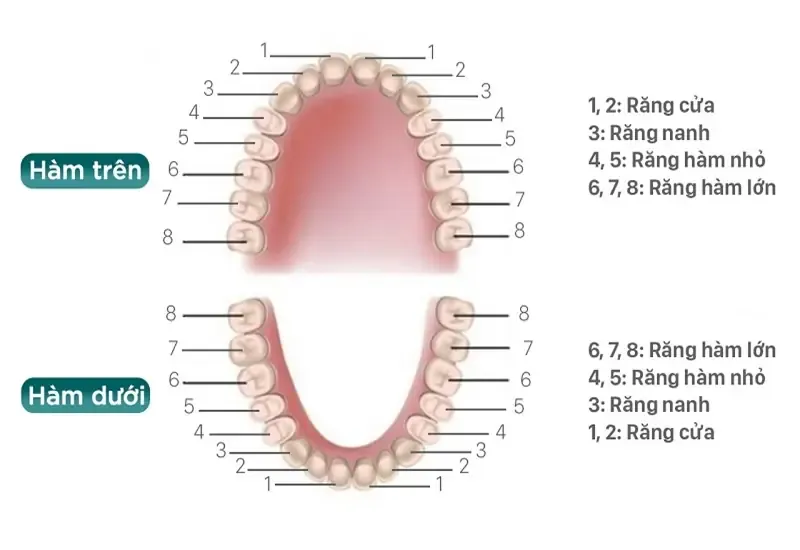

Hiểu biết về chiếc răng không chỉ giúp bạn nhận thức rõ hơn về sức khỏe răng miệng mà còn hỗ trợ việc chăm sóc và phòng